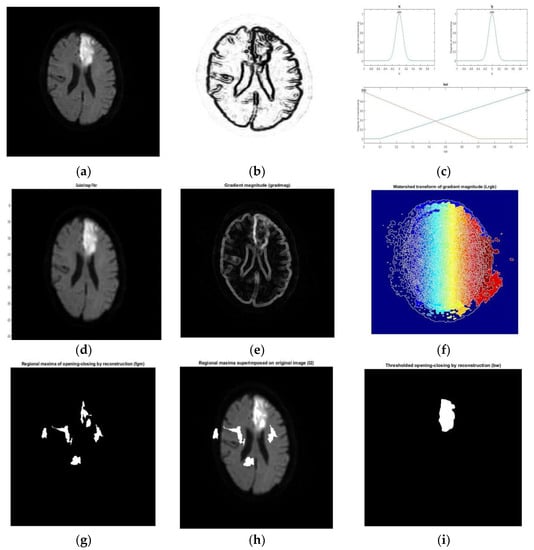

- Subudhi, A.; Jena, S.; Sabut, S. Delineation of the ischemic stroke lesion based on watershed and relative fuzzy connectedness in brain MRI. Med Biol Eng Comput. 2018, 56, 795–807. [Google Scholar] [CrossRef]

- Subudhi, A.; Jena, S.S.; Sabut, S. Automated detection of brain stroke in MRI with hybrid fuzzy c-means clustering and random forest classifier and applications. Int. J. Comput. Intell. Appl. 2019, 18, 1950018. [Google Scholar] [CrossRef]